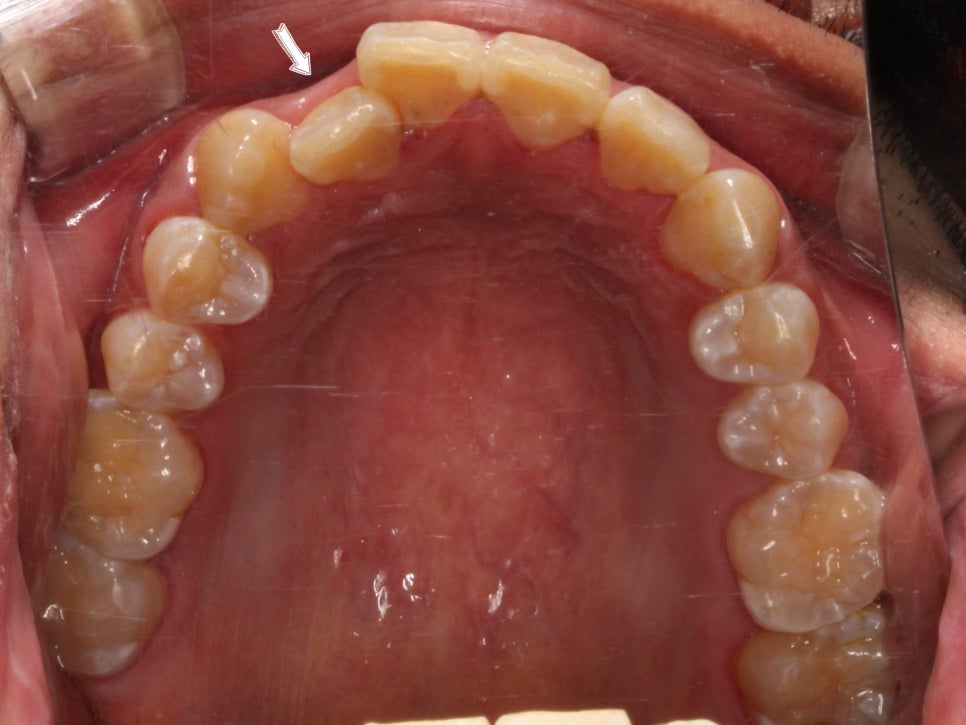

이렇게 씹는 면 사진으로 보면

#13이 튀어나왔다라기보단

#12가 상대적으로 들어가 있는 게 맞죠.

부분교정을 진행을 할 때에는

송곳니 위치와 구치부 교합관계를

꼭!!! 평가를 하는데요.

앞서 말씀드린 것처럼

송곳니 위치의 문제라기 보다

그 옆 치아가 상대적으로 들어가 있어서

덧니가 심해 보이는 모습이라,

제 기준으로는

충분히 부분교정이 가능해 보였습니다.